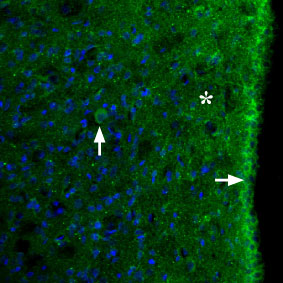

Expression of MC3R in rat brainImmunohistochemical staining of perfusion-fixed frozen rat brain sections using Anti-MC3 Receptor (extracellular) Antibody (#AMR-023), (1:100). Expression (green) appears in the hypothalamic periventricular region (horizontal arrow), in some nerve cells (vertical arrow), and in the neuropil (asterisk). Hoechst 33342 is used as the counterstain (blue).

Expression of MC3R in rat brainImmunohistochemical staining of perfusion-fixed frozen rat brain sections using Anti-MC3 Receptor (extracellular) Antibody (#AMR-023), (1:100). Expression (green) appears in the hypothalamic periventricular region (horizontal arrow), in some nerve cells (vertical arrow), and in the neuropil (asterisk). Hoechst 33342 is used as the counterstain (blue).